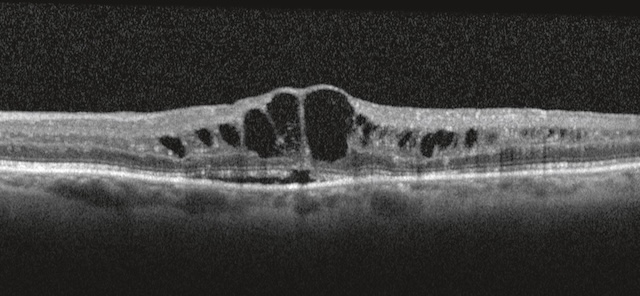

- • décollement de la rétine dû à la traction exercée sur la rétine par le tissu fibreux de soutien des néovaisseaux (prolifération fibrovasculaire) : on parle de décollement de rétine par traction (fig. 20.10) par opposition au décollement de rétine rhegmatogène induit primitivement par une déchirure de la rétine;

Fig. 20.10 A. Retinopathie diabétique proliférante avec fibrose prérétinienne (flèche bleue). B. Décollement de rétine tractionnel (flèche rouges), bien visible en OCT. Sur l’image A, un fond d’œil révèle une rétinopathie diabétique proliférante marquée par une fibrose prérétinienne épaisse et blanchâtre s’étendant en arc autour de la papille et de la macula. La traction générée par ces membranes fibrovasculaires est évidente, avec des plis rétiniens radiaires et un soulèvement localisé de la rétine. L’image B, en OCT, confirme un décollement de rétine de type tractionnel : la rétine est soulevée sans espace sous-rétinien liquidien net, et les insertions des tractions sont visibles de part et d’autre, souvent à proximité des néovaisseaux. L’ensemble témoigne d’un stade avancé de complication diabétique nécessitant une prise en charge chirurgicale.